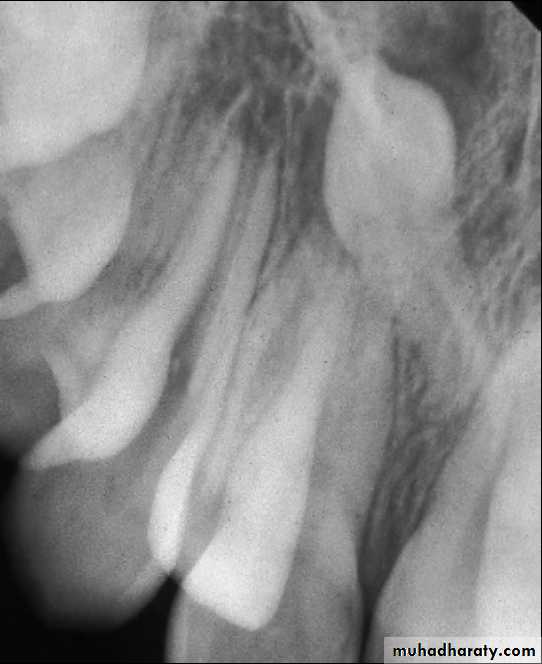

Most orthodontic assessment will include an ortho-pantomogram (OPG) and a lateral cephalometric view. Intraoral views are essential, however, for the management of unerupted maxillary anterior teeth due to the poor definition of the OPG in this region. In this situation, the OPT will usually be supplemented with periapical and/or upper anterior occlusal films.The use of ‘parallax’ analysis (Clark’s rule), in which two periapical views of the same area are taken from different angles, can be useful in determining whether the impacted teeth are buccal or palatal and therefore in planning the surgical approach to the teeth.